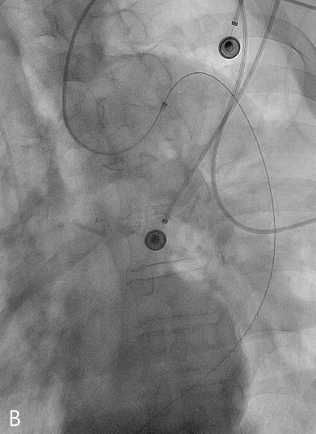

시술방법 및 재료

초음파 유도 하에 미세천자 세트를 이용하여 우측 총대퇴동맥을 천자하고 6-Fr sheath(Flexor Ansel Guiding Sheath, COOK, IN, USA)를 삽입하였다. 5-Fr Pigtail 카테터와 유도철사를 이용하여 신동맥하부의 복부대동맥까지 접근하고 조영제 주입하여 진성 내강의 형태를 확인하였다. 초음파 유도 하에 미세천자세트를 이용하여 좌상완동맥을 천자하고 6-Fr sheath (Flexor Ansel Guiding Sheath, COOK, IN, USA)를 삽입하였다. 이 후 대동맥궁의 근위부까지 Pigtail 카테터를 진입하여 시행한 대동맥조영술에서 대동맥궁에 진성내강과 가성내강 간에 교통하는 부위를 확인하였고, 그 원위부의 진성내강과 가성내강의 형태를 확인하였다. 유도카테터(5-Fr RDC catheter)를 조심스럽게 진성내강에서 가성내강으로 진입시키는데 성공하였다. 대동맥 진성내강, 가성내강, 그리고 우측 신장동맥에서 측정한 압력은 각각 120mmHg, 110mmHg, 그리고 62mmHg 이었다. 상완동맥으로 접근하여 가성내강으로 들어간 유도카테터와 sheath를 정방향(antegrade)으로 복부대동맥까지 진입하고, 대퇴동맥으로 접근하여 진성동맥에 위치한 유도카테터와 sheath를 역방향(retrograde)으로 하흉부대동맥까지 진입하였다. 이어 양측에서 시행한 대동맥조영술에서 flap의 위치관계를 평가하고 신장동맥상방에서 창냄술을 계획하였다. 복부초음파 유도하에 천자바늘(Transseptal Needle, COOK, IN, USA)을 진성내강에서 역방향으로 가성내강으로 천자하는데 성공하였다. 천자부위에 유도철사를 거치하고 5mm x 4cm, 10mm x 4cm, 18mm x 4cm, 25mm x 4cm크기의 풍선카테터(Sterling, Mustang, XXL Balloon dilatation catheters, Boston scientific, MA, USA, MAXI LD PTA dilatation catheter, Cordis, Baar, Switzerland) 로 순차적으로 혈관성형술을 시행하였다. 이 과정에서 대퇴동맥의 sheath를 8-Fr sheath로 교체하였다. 진성내강과 가성내강에 거치된 카테터로 시행한 조영술에서 진성내강과 가성내강에 균질하게 혈류가 흐르는 것을 확인하였다. 대동맥 진성내강 과 우측장골동맥에서 측정한 혈압은 각각 104mmHg, 90mmHg였다. 우측 총대퇴동맥의 sheath를 제거하고 혈관봉합기구(Angio-seal VIP vascular closure device, Terumo, Tokyo, Japan)로 천자부위를 지혈하고, 좌상완동맥의 sheath 제거하고 용수 압박으로 지혈 후 시술종료하였다(Fig .2).